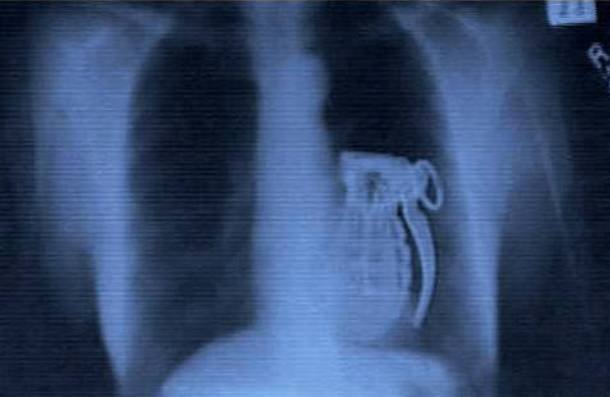

Ручная граната

А вот один радикальный террорист засунул в себя оружие вполне добровольно. Злодей планировал спрятать ручную гранату в желудке и устроить диверсию. Самопожертвования ему, конечно, не занимать, но вот на ум места не осталось: он попросту не смог активировать гранату изнутри. Снаряд обнаружили, когда он пытался покинуть город.